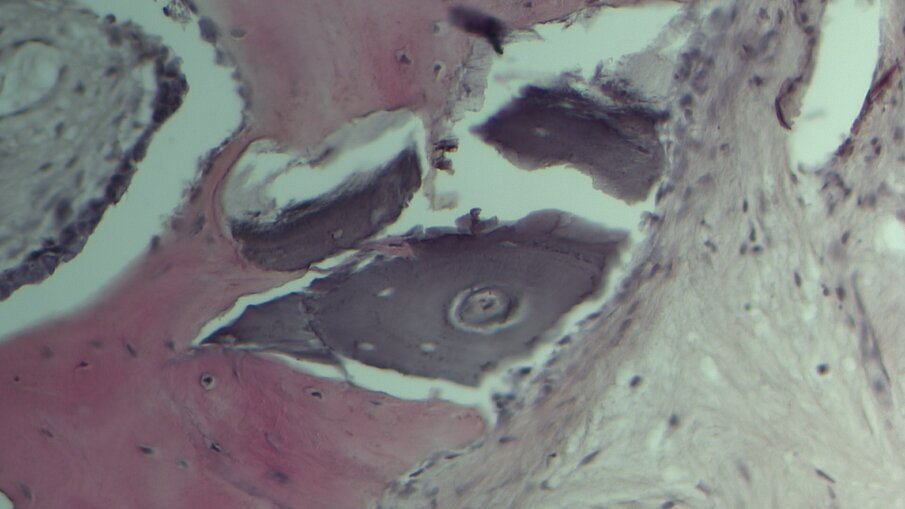

Quattro pazienti con severa atrofia verticale dell’osso alveolare della regione posteriore del mascellare superiore, che necessitavano di una riabilitazione implantoprotesica unilaterale della zona edentula, sono stati trattati con la tecnica del Sinus Pack. Dopo 6 mesi è stata eseguita una TC per valutare il volume osseo ottenuto, sono stati inseriti gli impianti ed è stata inoltre prelevata una carota ossea di 4 mm con una fresa carotatrice ossea. Sono stati sottoposti a trattamento tre uomini e una donna (range di età tra 36 e 74 anni); non sono state registrate complicanze intra o postoperatorie. Confrontando le misurazioni eseguite sulla TC preoperatoria e dopo 6 mesi dall’intervento, è stato riscontrato un guadagno verticale di osso pari a 6,95 mm (Figg. 1-4). Nella valutazione dell’analisi istologica e istomorfometrica della carota ossea prelevata si è riscontrato un completo riassorbimento della membrana, una neoformazione ossea e solo una piccola percentuale di innesto ancora presente (Figg. 5-7).